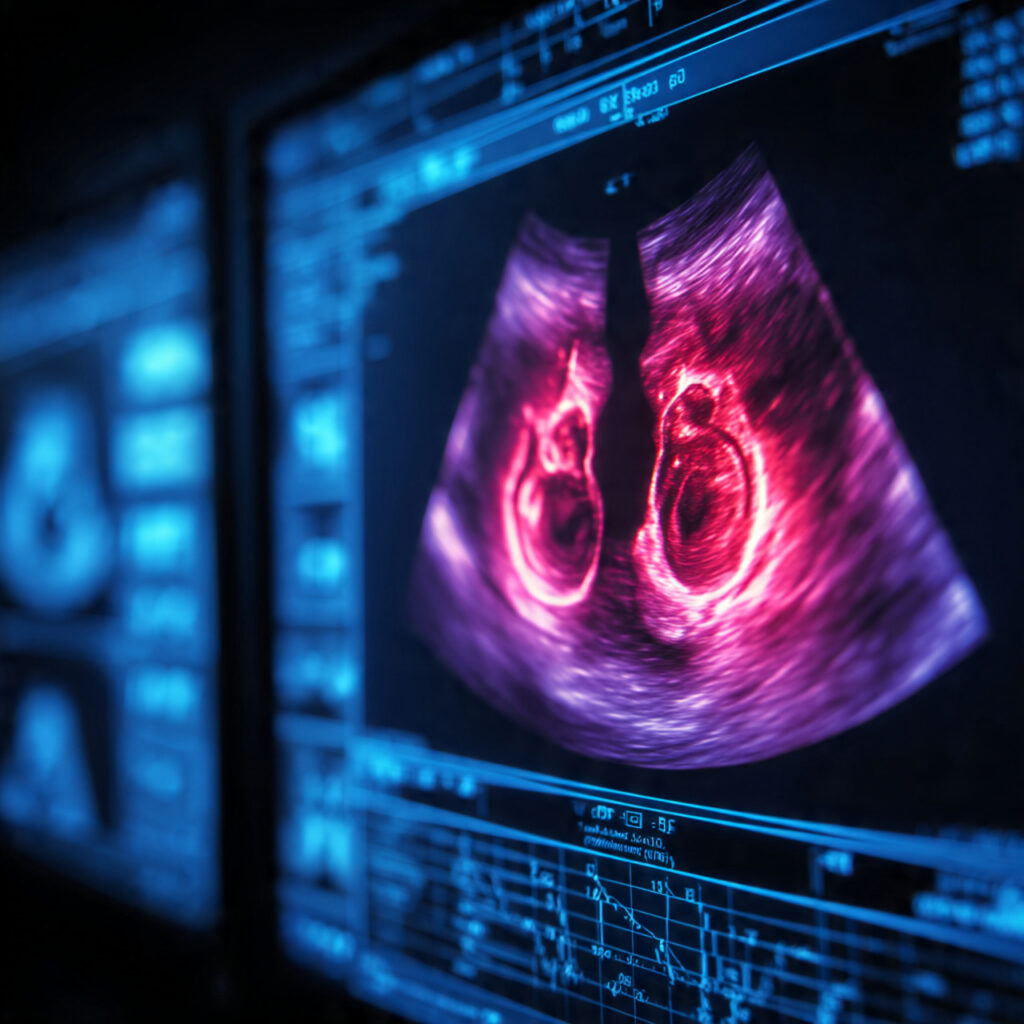

Why Do Doctors Recommend More Frequent Scans in Twin Pregnancy?

Twin pregnancy is a beautiful experience, but it also needs extra care, closer monitoring, and more frequent scans than a single-baby pregnancy. Many parents feel confused or worried when doctors tell them to come for scans more often. But the truth is: These extra scans keep both babies safe

In this detailed guide, you will learn why twin pregnancies need more scans, what each scan checks, what risks are monitored, and how Nisarga Diagnostics Bangalore supports twin mothers with advanced pregnancy ultrasound services.

🌼 What Makes Twin Pregnancy Special?

Twin pregnancy means growing two babies together inside one womb. This makes your pregnancy more unique and sensitive than normal pregnancies. Some twins share the same: